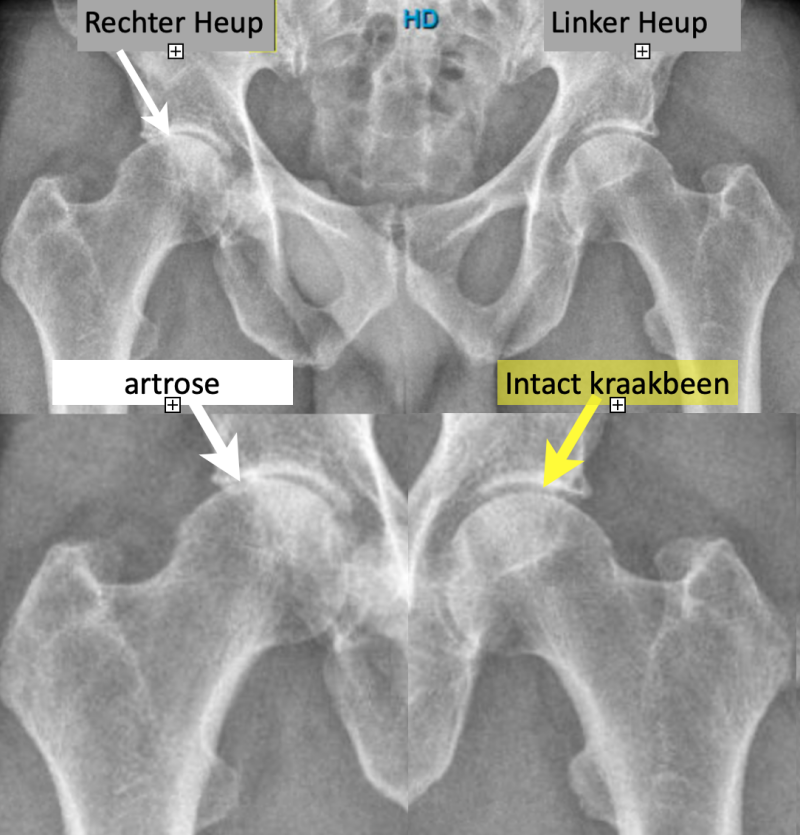

Röntgenfoto van het bekken (boven) en uitvergroting van de heupen (onder).

Artrose rechter heup en normale linker heup (re in beeld) - de kraakbeenlaag is verdwenen aan de buitenzijde van de rechterheup.

Op een Röntgenfoto van een normale heup zonder artrose lijkt er ruimte tussen de kop en de kom. Dit is echter geen ruimte maar de kraakbeenlaag die de botdelen van elkaar gescheiden houdt (kraakbeen bestaat voor 80% uit water en laat daarom de Röntgenstralen door) .

Als deze kraakbeenlaag beschadigt en verdwijnt is er bot op bot contact.